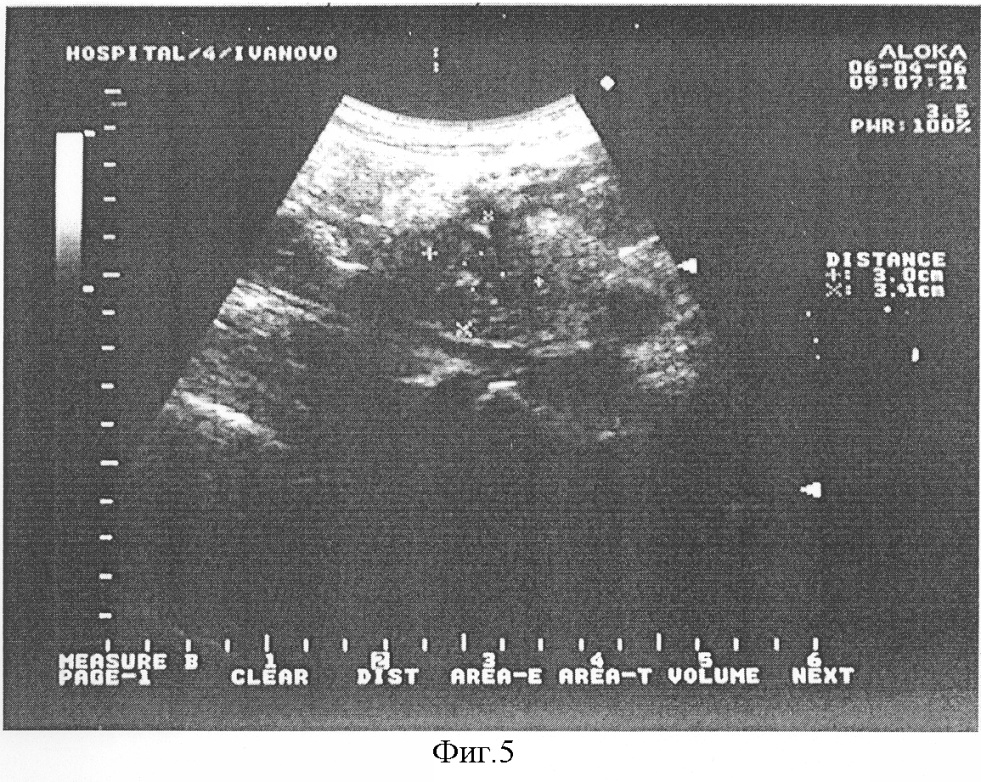

Пример. Больной К., 55 лет, И/Б № 1695, поступил в клинику 19.03.2006 года с жалобами на боли в верхней половине живота, частую рвоту, снижение массы тела. При рентгеноскопии желудка и двенадцатиперстной кишки выявлена компрессия нисходящей части двенадцатиперстной кишки за счет увеличенной головки поджелудочной железы (фиг.3). При выполнении УЗИ диагностировано полостное образование в проекции головки поджелудочной железы размерами 5,6×4,8 см (фиг.4). В плановом порядке 26.03.2006 г. произведена операция – наложение V-образного цистодуоденоанастомоза. В послеоперационном периоде на контрольной эхограмме 06.04.2006 в области головки поджелудочной железы (на месте псевдокисты) определяется образование размерами 3,0×3,1 см без полостного компонента (фиг.5). Пациент выписан в удовлетворительном состоянии, проходимость двенадцатиперстной кишки восстановлена, полость панкреатической псевдокисты не визуализируется.